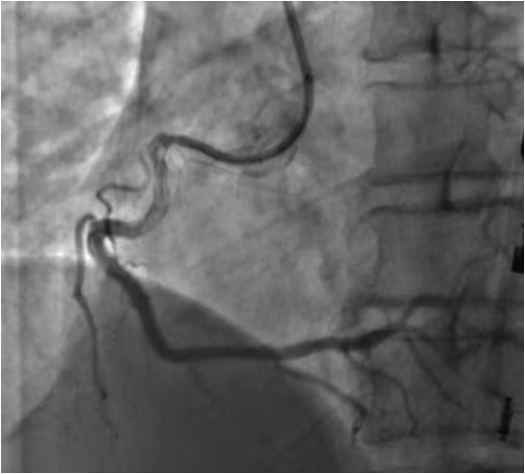

09.03入院

09.04